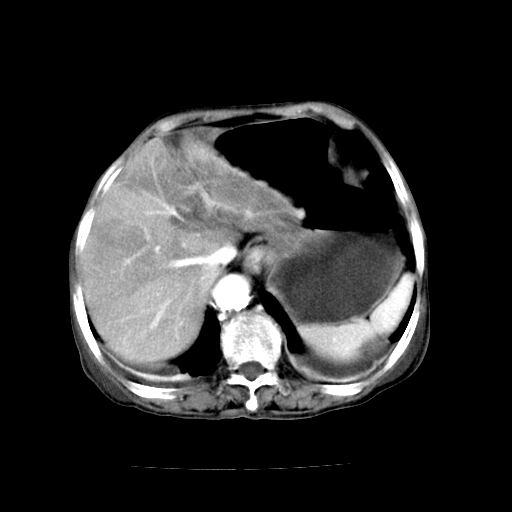

标题: CT19149:女,68岁,腹胀、恶心两周。 [打印本页]

女,68岁,腹胀、恶心两周,先做ct平扫,当时家属不同意强化,6天后家属要求增强扫描。

1、胃窦癌; 2、局灶性脂肪肝。

1、胃窦癌?建议行胃镜!; 2、局灶性脂肪肝。

1.局灶性脂肪肝;2.胃窦癌可能,建议行进一步检查。